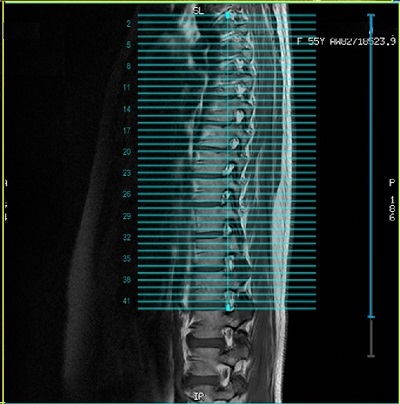

3. Check the coil extent lines to confirm coil coverage of slice locations. The blue lines should encompass the graphic slice lines.